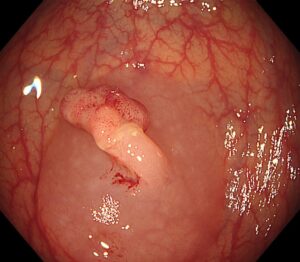

👉 生理食塩水をポリープの下に注入し(写真3)、 粘膜下層がふっくらと盛り上がりました(写真4)

(写真4)